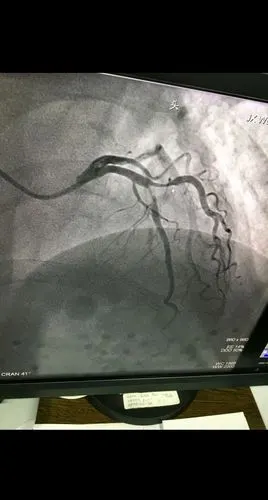

冠脉造影结果显示血管狭窄达75以上就要放支架心内科医生说未必

清晰的心脏冠脉造影图片!

冠状动脉造影,左冠状动脉造影

心脏循环有没有狭窄,下面这张图是一个有糖尿病,高血压的患者做的造影